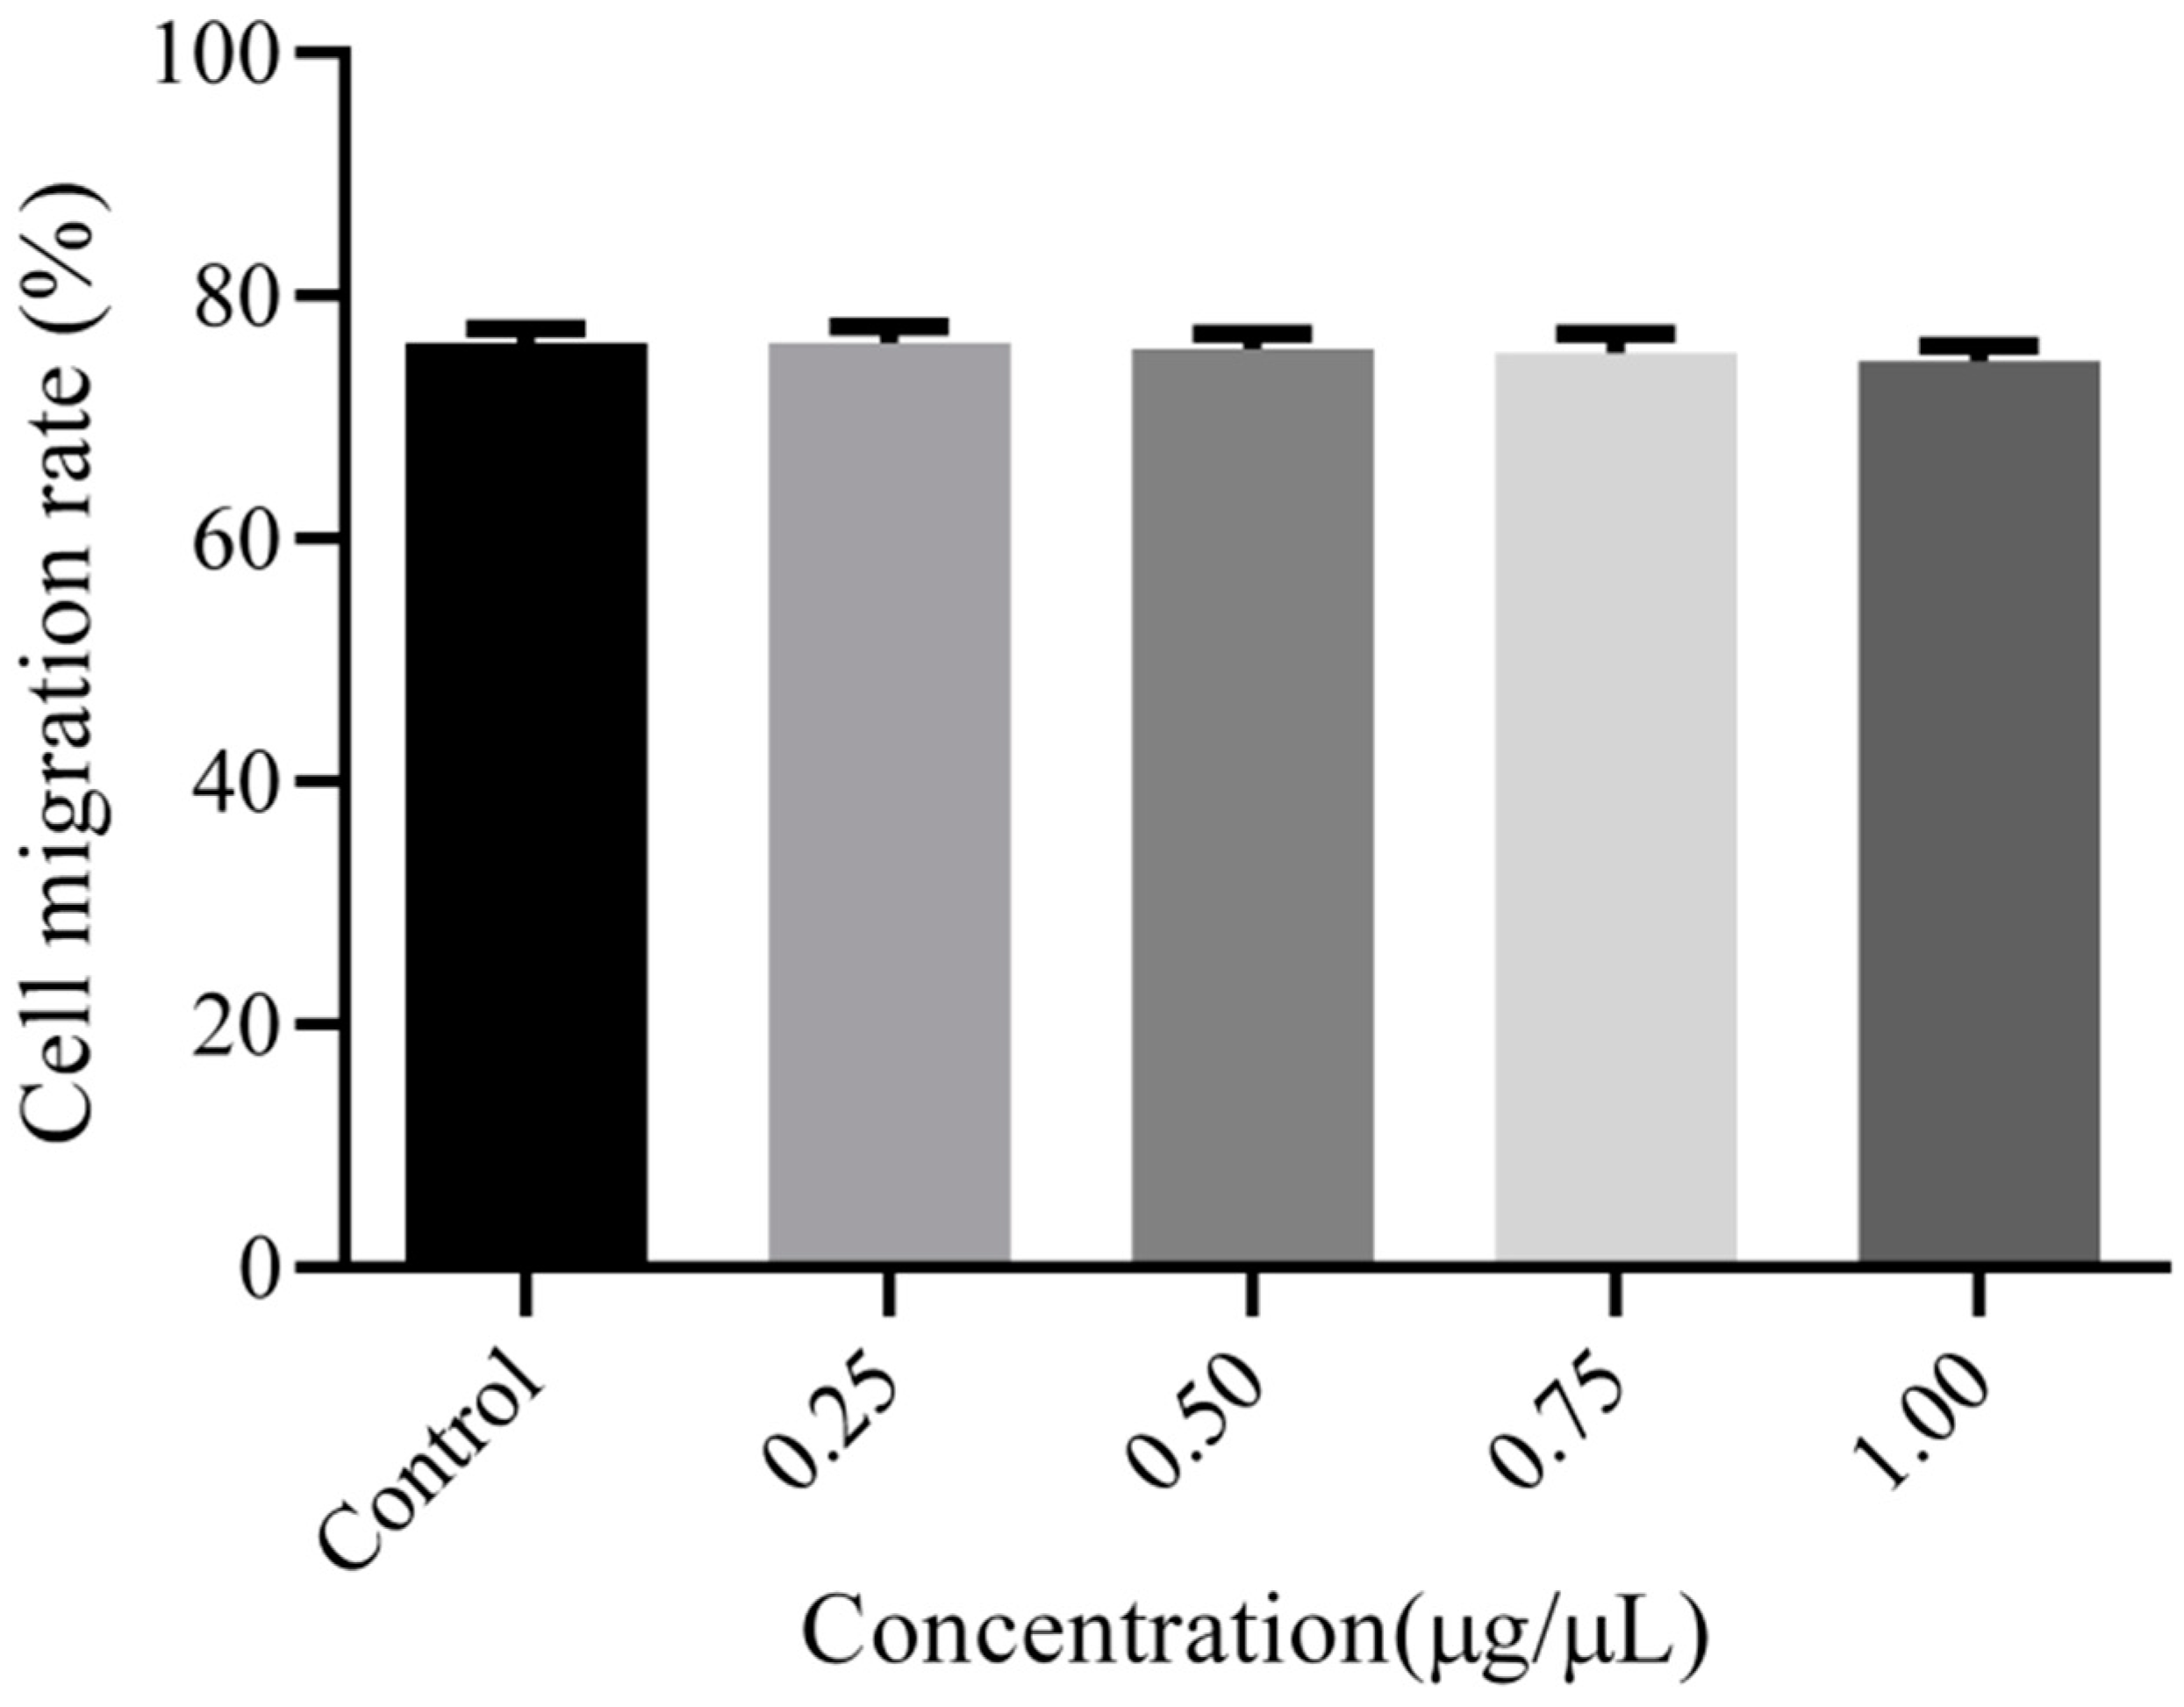

2.7. Cell Migration Test

3.4. Cell Migration Analysis